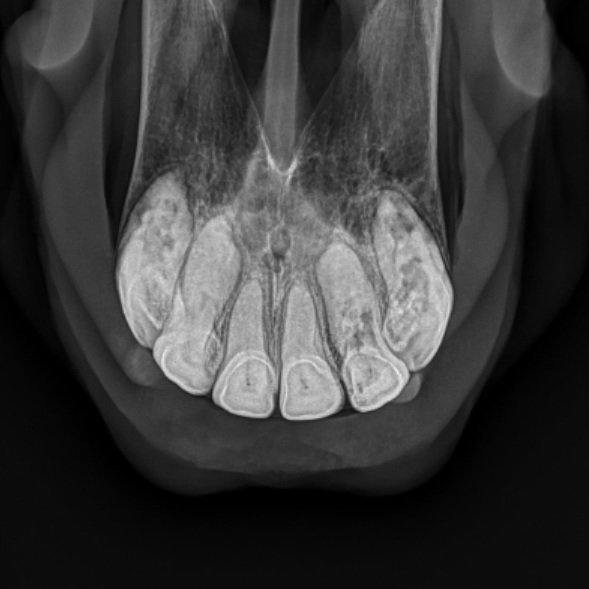

EOTRH

Equine Odontoclastic Tooth Resorption and Hypercementosis (abbreviated for obvious reasons to ‘EOTRH’) is a very painful condition involving the destruction of 1 or more teeth with or without excess cementum deposition. The incisors are most commonly affected, but occasionally the canine teeth or premolars are also affected. The cause of this disease is still unknown, but likely involves multiple contributing factors. Your veterinarian will check your horse for evidence of this disease at each dental. Radiographs can be used to evaluate the degree of resorption of the tooth roots. Symptoms include: pain biting with the front teeth (such as when biting carrots), quidding feed, gingivitis, gumline recession, and abnormal cementum deposition at the gumline. There is no known treatment aside from removal of the affected teeth. Luckily, horses tend to do very well and go on to live a pain-free life with removal of the affected teeth.